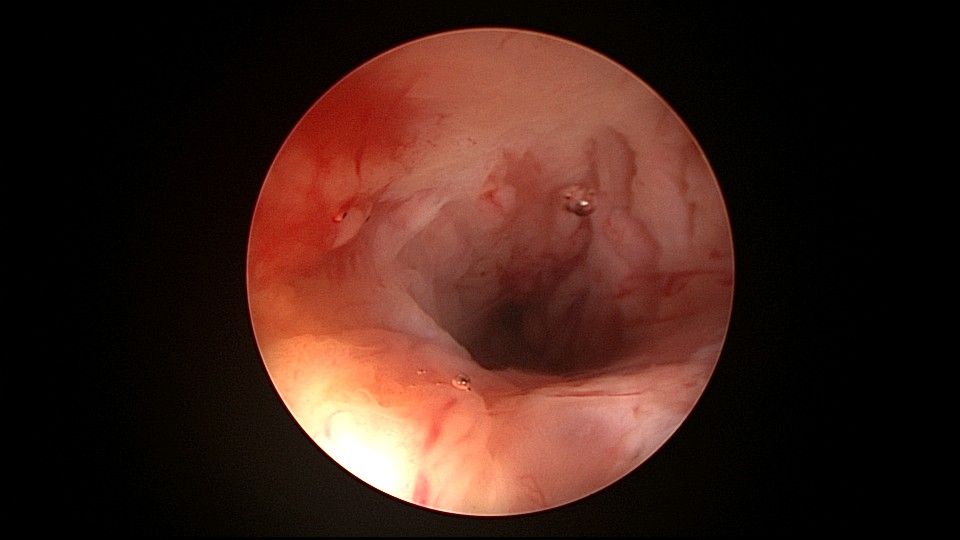

患者42,G3P1,顺产1次。子宫腺肌症伴腺肌瘤,逐渐加重的痛经,2024年11月起皮下注射亮丙瑞林3个周期,出现潮热出汗症状。2025年4月,要求放置曼月乐环并固定,子宫后位,宫深9cm,宫腔上段右侧粘连,宫腔下段宽大。4-0不可吸收线将曼月乐缝合固定于宫腔上段后壁,缝线上靠近曼月乐间距1cm左右打3个结,缝合1针,将1个线结拉过缝合处肌层,利用子宫肌层线结卡压固定曼月乐,避免打结推结。术后多次复查B超,曼月乐位置正常,环顶端距宫底1.6cm。